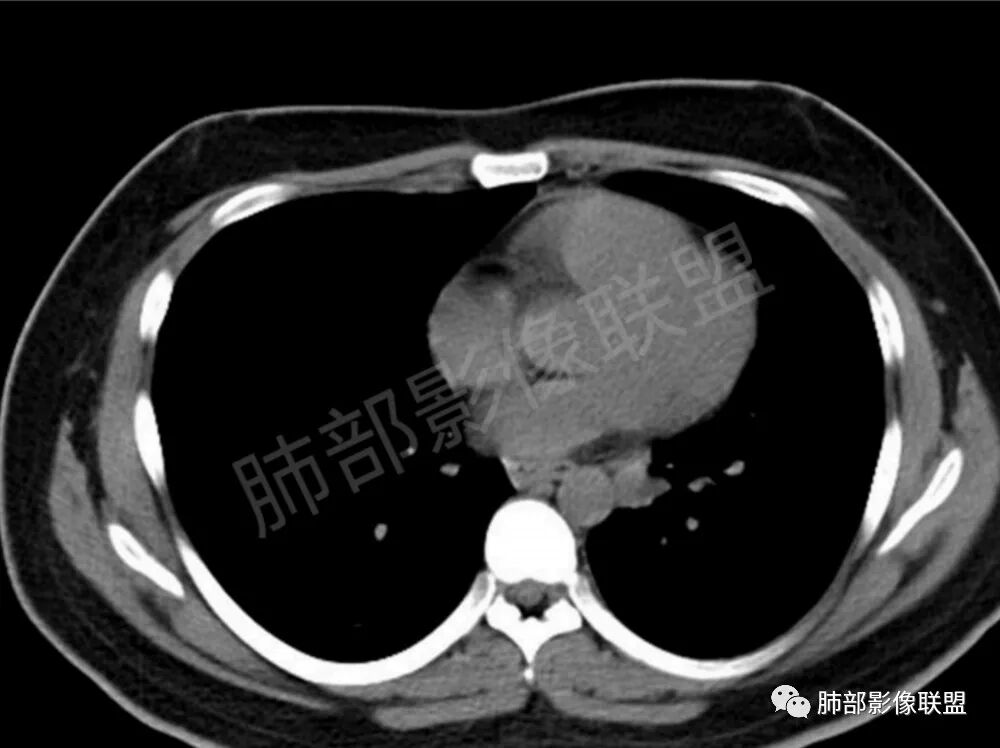

两肺多发结节性,大部分位于胸膜下,部分结节周围可见晕征。局部结节内可见扩张的支气管,纵隔淋巴结大,脾大,22岁男,HIV阳性,常规先考虑隐球菌。鉴别淋巴瘤,结核,马儿。

青年男性,咳嗽、少许咳痰半年,慢性病程,病程中无明显感染毒血症状,查TB-DNA阳性,HIV-Ab阳性,CA19-9、铁蛋白升高,CT提示双肺多发斑片状、团块状、结节状高密度影,可见一薄壁空洞,部分病灶可见支气管进入,病灶于肺外围区域优势分布,肺结核诊断明确,但是患者CT与结核影像不符,考虑二元论,复合感染:1.隐球  2.奴卡(肺部病灶气、血同现)3.AIDS机会性肿瘤:淋巴瘤

男,22,半年前咳嗽伴少痰,查HIV阳性,痰查TB阳性,既往有肺部斑片影伴空洞、纵隔淋巴结肿大、脾大。SCC、CA50、CA199、FER增高,此次胸部CT:两肺多发结节影,部分沿血管束分布,部分贴胸膜下,大小不一,密度不一,部分较散、边缘模糊,部分较实、圆钝、周围模糊晕,部分结节有支气管进入穿行自然,部分结节有血管分支自如通过。考虑HI∨相关淋巴增殖类病变,淋巴瘤?LYG?鉴别PC、TB。

青年男性,半年前咳嗽,HIV阳性,结核DNA阳性,肿标糖类抗原和铁蛋白增高。外院影像有纵隔淋巴结增大伴脾大,肺部病灶空洞。现在影像:肺内多发沿支气管分布(有支气管充气征,长轴沿支气管分布)及胸膜下分布(平行于胸膜)的大小不等结节,个别伴有空洞,双侧腋窝淋巴结肿大。纵隔图片不够,是否还有淋巴结肿大未知,脾脏未显示。

1、HIV相关淋巴瘤,有HIV阳性,有纵隔及腋窝淋巴结肿大,肺内病灶沿支气管分布(中轴淋巴间质)及胸膜下分布(周围淋巴间质),有脾大,这个是必须要考虑的。但是原来的影像是肺斑片影伴空洞,又有疑问,需要穿刺明确。